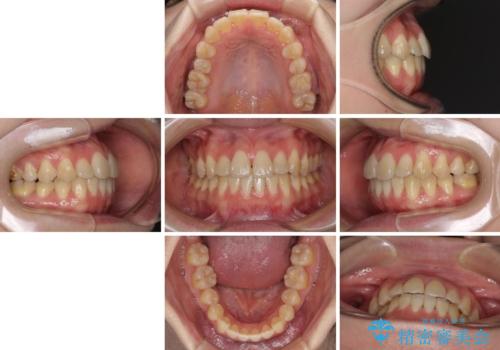

ハーフリンガル 反対咬合の改善

- 前歯の反対咬合を気にして来院された患者様です。

目立ちにくい装置での治療をご希望とのことで、上顎が裏側装置、下顎が表側装置のハーフリンガルにより矯正治療を行うこととしました。

下顎の歯列全体を後方に動かす場合、さまざまリスクを伴うため慎重に行う必要があり、さらには移動量に限界があるため、治療計画は無理のないものとしなければなりません。

下顎左右の奥にアンカーボルトを使用して、無理のない範囲で後方に移動させ、きれいに仕上げることができました。